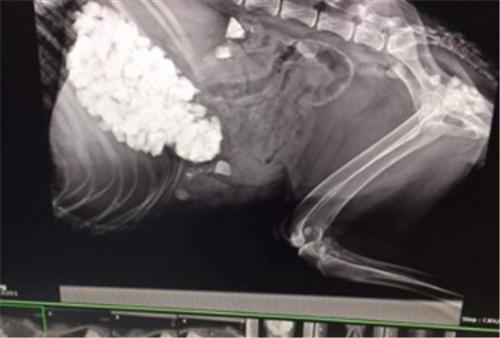

六、误食异物

狗狗总是容易对一切事物充满好奇,时常也会出现吞食异物的现象,狗狗胃内异物长期不被消化会导致呕吐和食欲不振。根据胃内存有的异物大小不同,临床症状有所差异。当胃内异物是金属或是锐性物体时(如鱼钩、玻璃、铁丝等),临床上出现急性胃炎的症状。

应对方案:及时带去宠物医院检查身体状况,多给狗狗补充微量元素